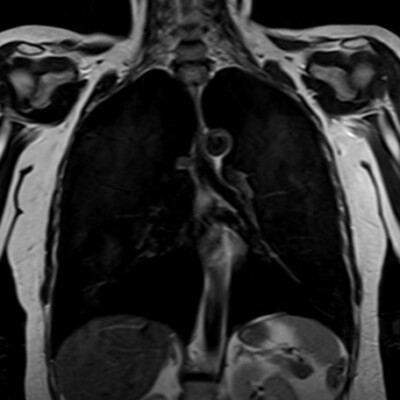

Full Body MRIs

A comprehensive full-body MRI scan designed to detect potential health concerns early, providing a detailed, radiation-free assessment for proactive and preventative care.

Specific Body MRIs

Get a specific body, organ, looked at with advanced MRI imaging